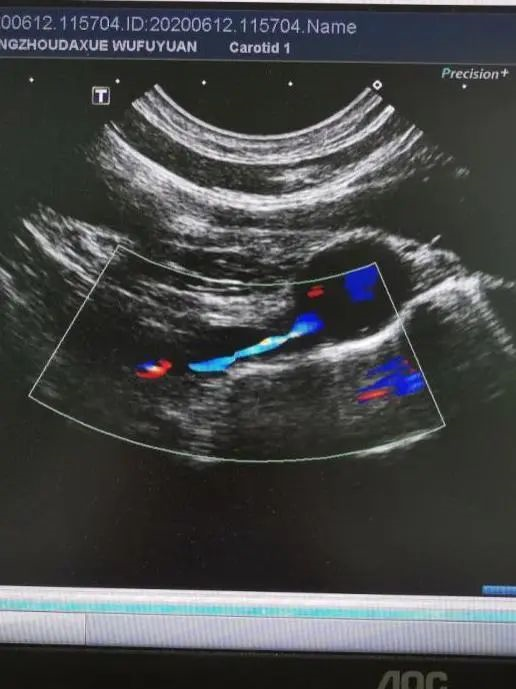

郑州大学五附院作为国家高级卒中中心、国家脑卒中筛查与防治基地,医院超声诊断科委派主治医师刘会苗到北京宣武医院学习颈动脉超声和经颅彩色多普勒超声(TCCD)/TCD(声窗不好病人)一体化评估,即由同一个大夫对颈动脉及脑动脉进行整体化评估,对疾病的诊断更加全面,减少了漏诊和误诊,节约了病人的时间。

经过学习,颈动脉超声比以前更加关注了椎动脉开口处疾病,给后循环病变提供了更多的信息。已开展对颈动脉狭窄程度、侧枝循环、锁骨下动脉狭窄程度的评估,并为颈动脉支架及剥脱术进行术前评估、术中监测、术后随访。